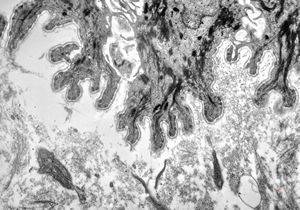

M, 28y. | leishmaniosis … skin of the cheek

M, 28y. | leishmaniosis … skin of the cheek